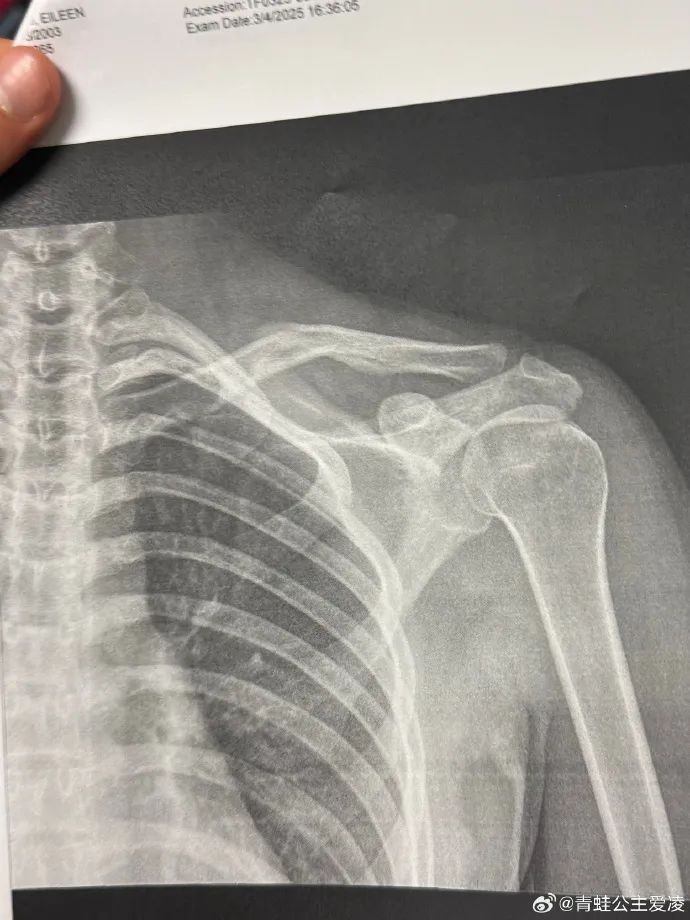

北京时间3月9日,中国自由式滑雪名将谷爱凌在个人社交媒体公布锁骨受伤检查结果,并用“心碎”表达了自己的心情。不少网友安慰她,希望她好好休养,早日康复。相关话题登上网络热搜。

检查报告显示的日期是3月4日,目前尚不得知谷爱凌本次的伤病是新伤还是旧伤。